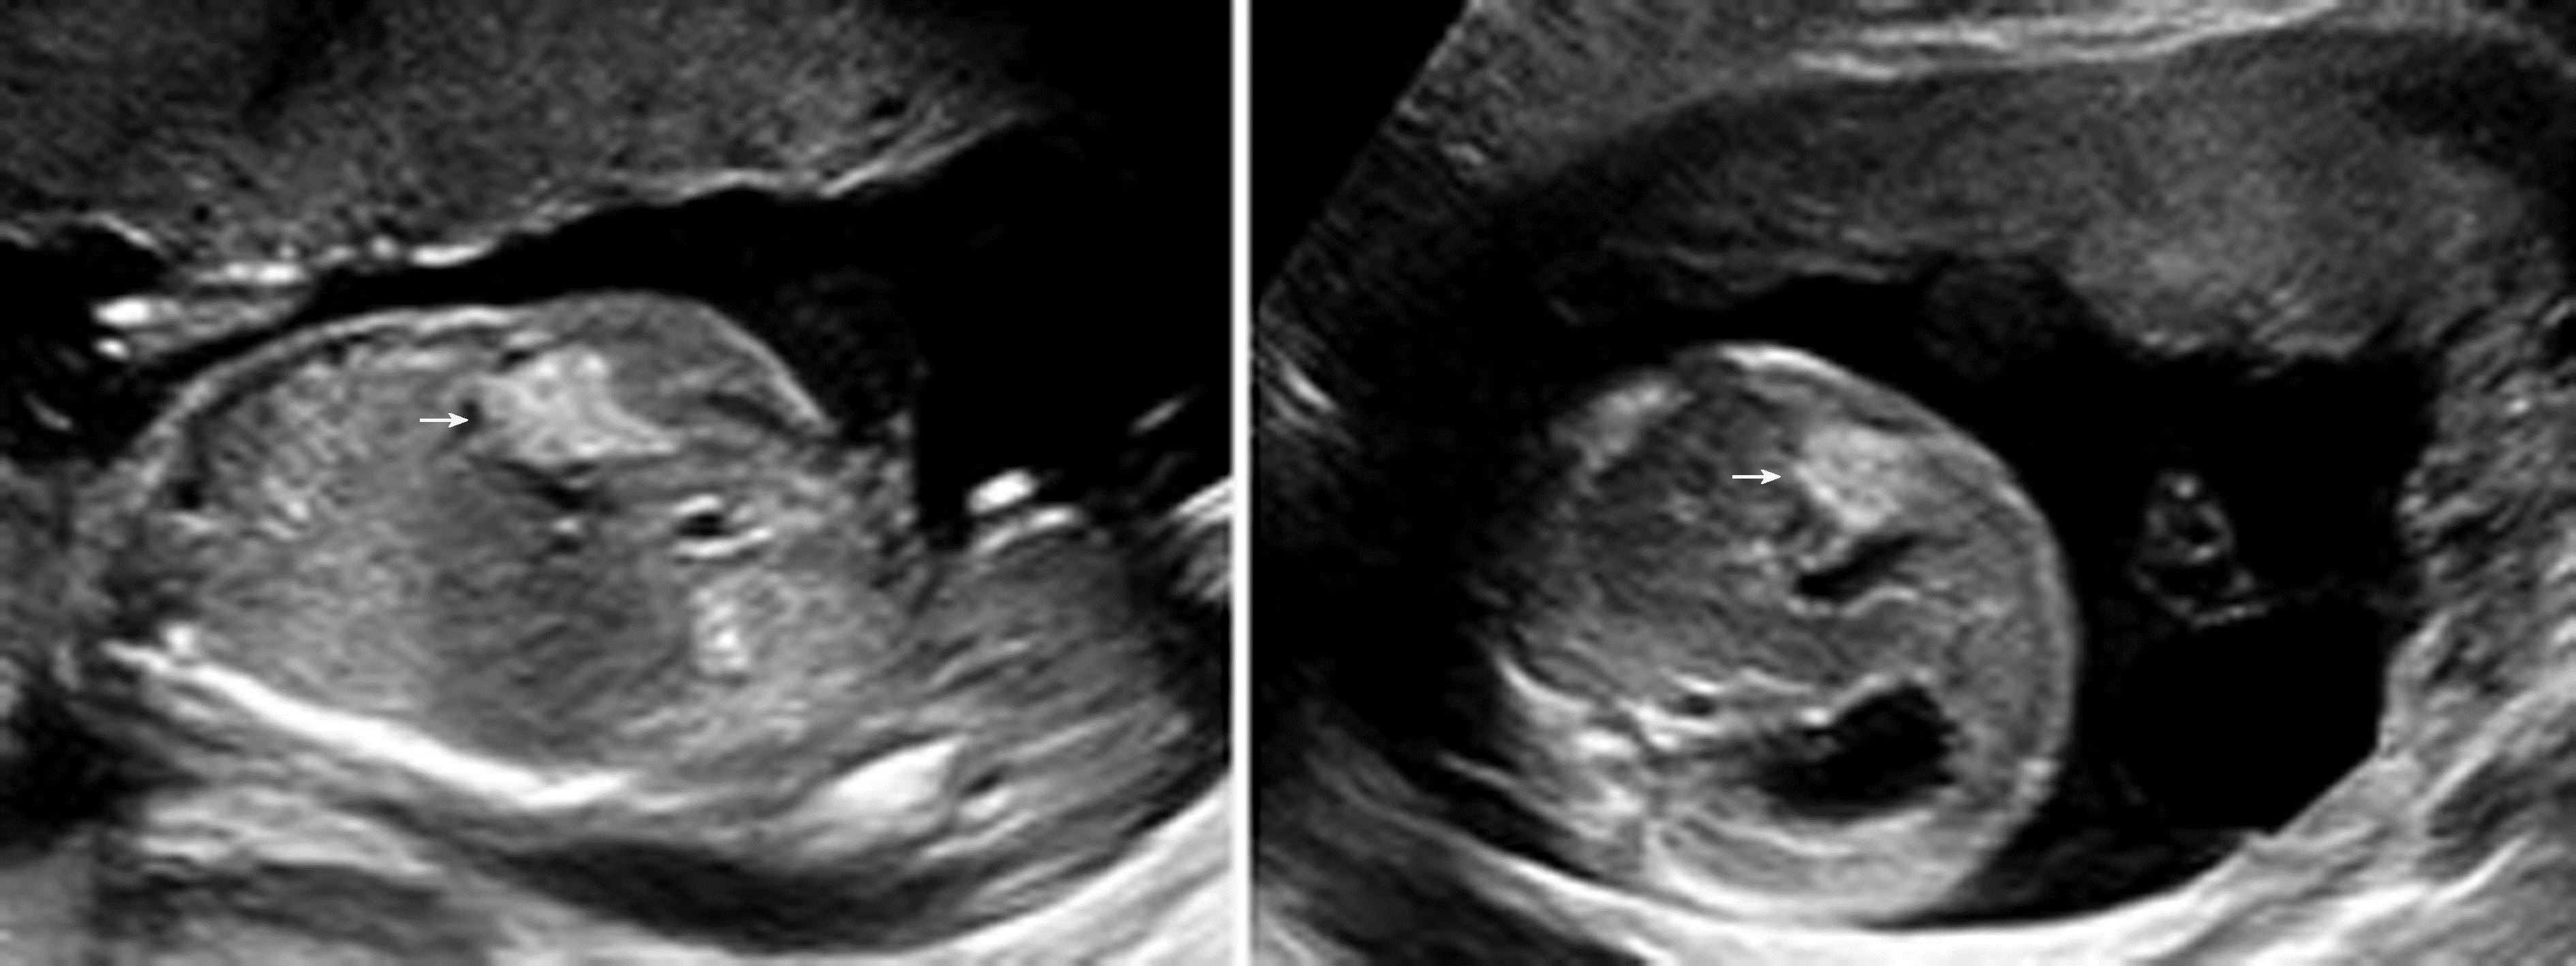

肝脏肿瘤少见,产前超声表现为肝内单个或多个低或高回声团块,部分可有钙化。文献报道的胎儿肝脏肿瘤有肝囊肿、肝血管瘤、肝母细胞瘤、肝腺瘤、错构瘤、肝转移性肿瘤等(图2)。较大的胎儿肝血管瘤及肝母细胞瘤,可导致肝脏增大,多为混合性回声肿块。较大的胎儿肝血管瘤可出现广泛的动静脉瘘而导致胎儿高心输出量性心力衰竭,进一步发展可导致胎儿水肿,但这种情况相当罕见。诊断先天性肝囊肿时,应关注与胎儿胆囊、胎儿肝内段脐静脉曲张等相鉴别。肝肿瘤较大伴胎儿水肿者,预后不良。肝母细胞瘤及转移性肝肿瘤预后不良。单纯肝囊肿预后良好,但合并胎儿多囊肾者预后不良。

图2 孕29周胎儿肝脏血管瘤